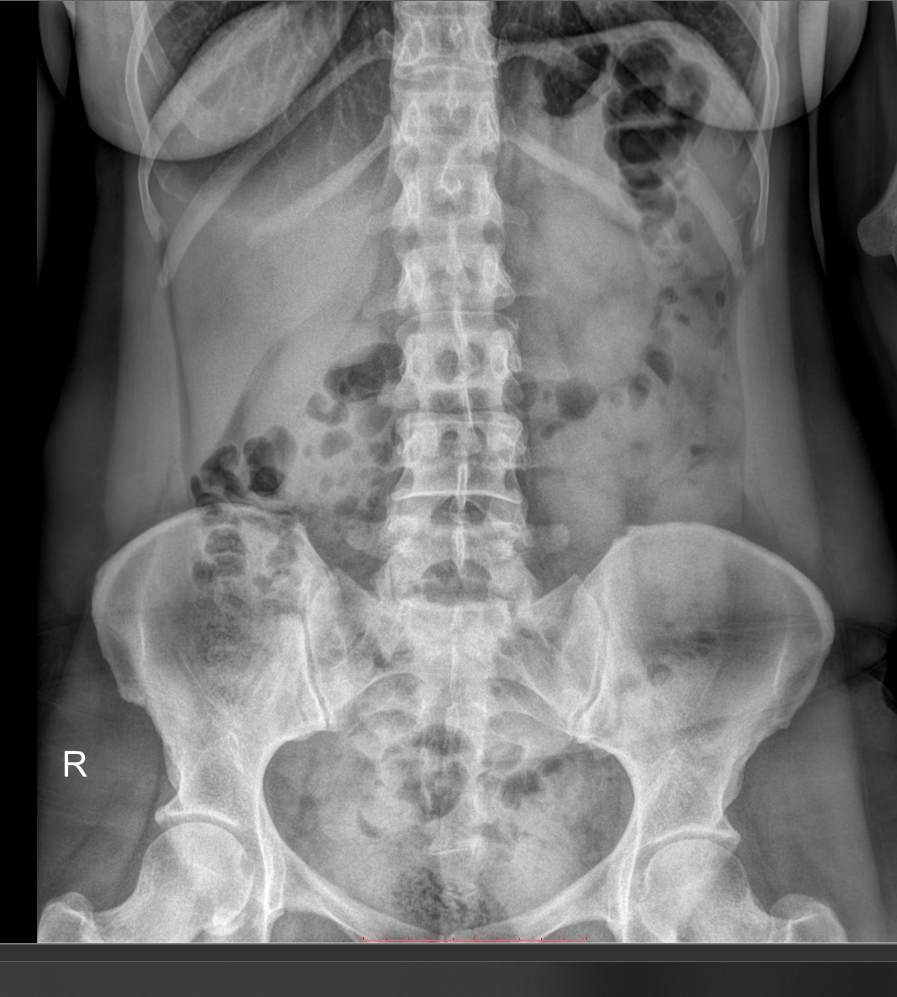

Рентген почек, мочеточников, мочевого пузыря (обзорный)

Обзорный снимок мочевыделительной системы обычно является первым этапом в ее диагностике. Часто он предшествует экскреторной урографии, но может быть и самостоятельной процедурой. Современное цифровое рентгеновское обследование основано на тех же принципах, что и аналоговое прошлых поколений. То есть в результате исследования мы получаем классический черно-белый снимок. Но сейчас для диагностики применяется минимально возможная доза облучения, которая позволяет безопасно делать несколько снимков подряд. Именно такое оборудование используют в клинике «Доступная медицина».

Что показывает обзорный рентген мочевыделительной системы

У здорового человека обзорный снимок покажет:

- Тени почек и мочевого пузыря;

- Мочеточники ― только при значительных изменениях;

- Нижние грудные, поясничные позвонки, ребра, тазовые кости;

- Тени поясничных мышц.

На рентгенограмме будут видны такие патологии, если они есть:

- Увеличение или уменьшение почек в размерах ― признак врожденной аномалии, воспаления и других заболеваний;

- Камни в почках и мочевом пузыре;

- Коралловидные камни в почках;

- Конкременты в желчном пузыре;

- Флеболиты ― камни вен малого таза;

- Опухоли и очаги склероза в костях малого таза;

- Обызвествленные хрящи ребер и лимфоузлы;

- Инородные тела.